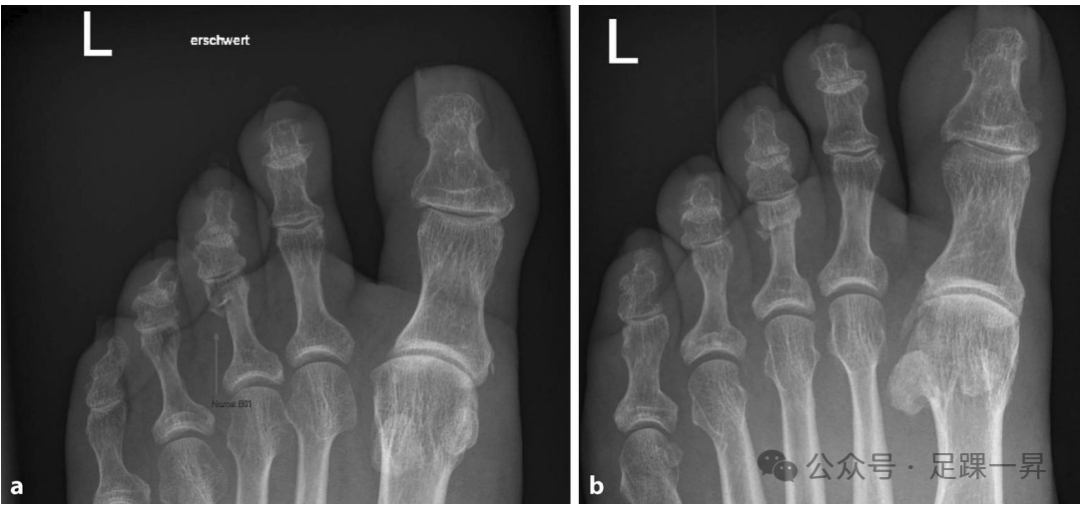

▲图示第3趾近端趾骨无移位骨折,保守治疗。a 正位X线片,b 斜位X线片。